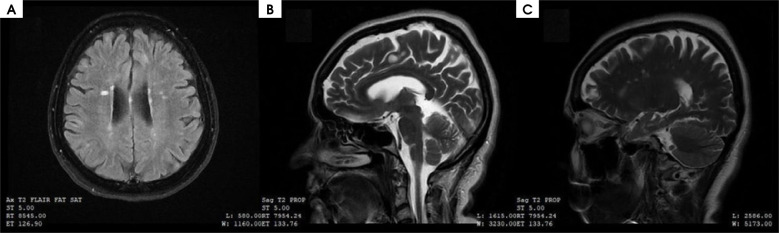

Case description: A 54-year-old female patient with quadriparesis, superficial sensory disturbance and gait and balance disorders was diagnosed with primary progressive MS according to McDonald's criteria. The magnetic resonance images were typical for MS. Previously, in 2013, she was diagnosed with SLE, treated successfully, and is currently in remission. After excluding neuropsychiatric lupus, ocrelizumab treatment was administered, with good clinical results.